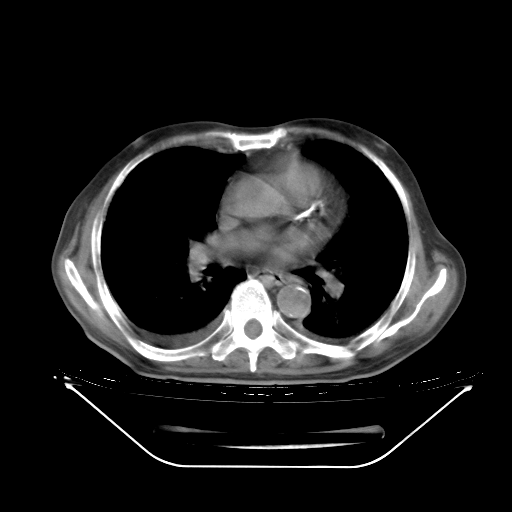

5月9日肺部CT(在4月27日齐鲁医院肺部CT描述部分肺组织磨玻璃样改变,12天后肺组织广泛磨玻璃样改变)

2009年5月9日肺部CT

大致读了系列胸部CT:纵隔窗无明显异常,肺窗:从4、27至今:主要是双肺中下野外带可见毛玻璃样改变,目前处于急性肺泡炎阶段,至于原因考虑1、结替组织或胶原血管性疾病所致?2、恶性疾病如恶组在肺部所致的表现或细支气管肺泡癌?3、药物或其它原因如肺蛋白沉着症所致肺泡炎目前不太可能?总之,明天就去请我院的呼吸科、感染科、血液科和临免专家会诊哈。